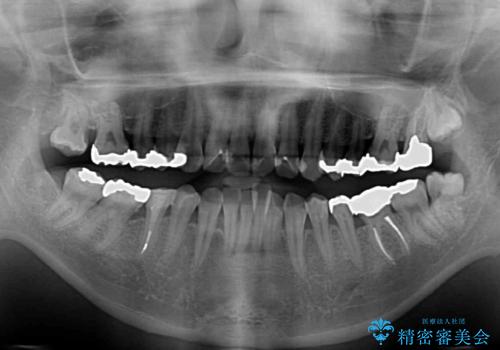

- 上下のデコボコと奥歯の咬みにくさを気にして来院された患者様です。

上顎骨の幅が下顎骨よりも小さいので、拡大装置により骨幅を広げて上下関係を改善し、その後インビザラインにて歯並びを整えることとしました。

上下の骨幅を改善したことで、スムーズに歯列矯正を行うことができました。

矯正治療中に近医で銀歯を外す治療を開始したため、治療後に奥歯の咬み合わせが不十分ですが(こちらは近医での治療により改善するとのこと)、歯列と咬み合わせが改善され、患者様には大変満足していただきました。